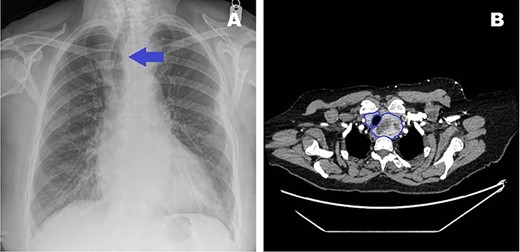

An 83-year-old female with symptomatic (New York Heart Association Functional Classification III symptoms) critical aortic stenosis (AS), (peak gradient 105 mmHg) was admitted for elective AVR via mini-sternotomy after being found unsuitable for transcather aortic valve implantation. At pre-admission, the patient was incidentally found to have subclinical palpable thyroid goitre with tracheal deviation (Fig. 1A). A subsequent computed tomography (CT) scan showed an 8-cm paratracheal thyroid hemi-goitre, extending retrosternally and abutting the ascending aorta and arch (Figs 1B and2).

(A) Pre-admission chest radiograph highlighting visible tracheal deviation due to goitre (blue arrow). (B) Transverse CT image showing goitre relation to trachea (blue outline).